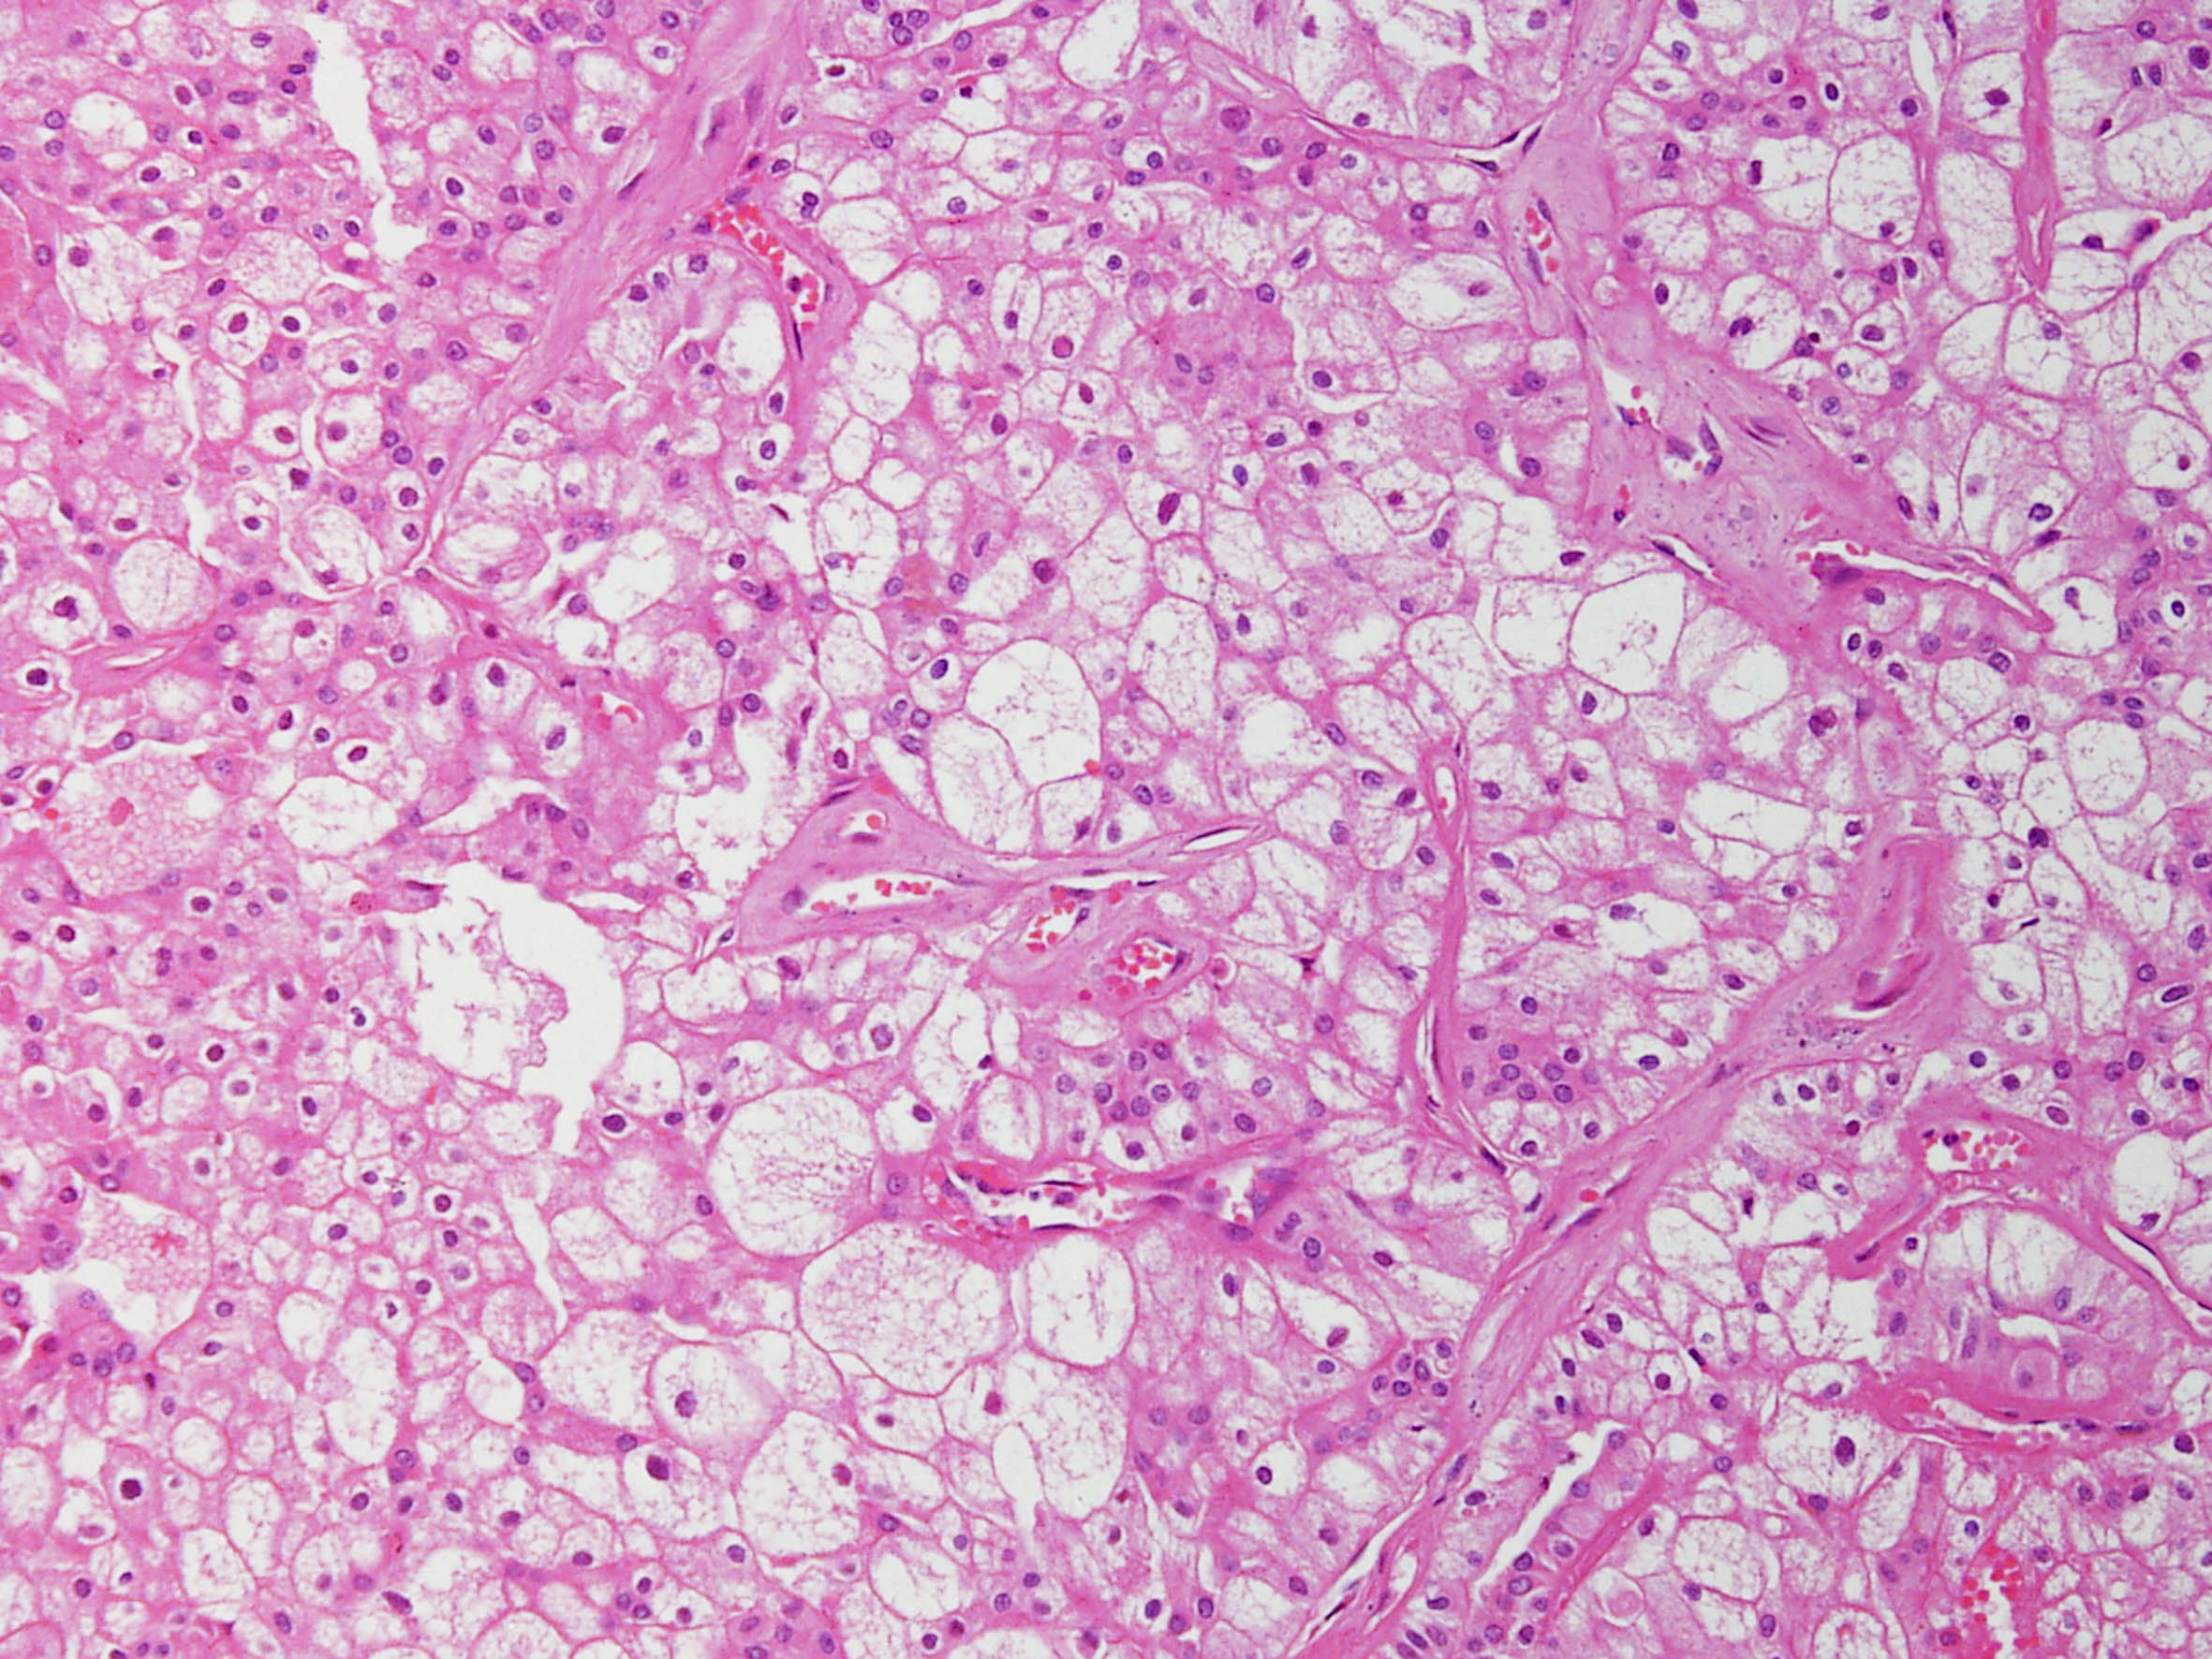

Consensus grade: Chromophobe RCC

Chromophobe renal cell carcinoma